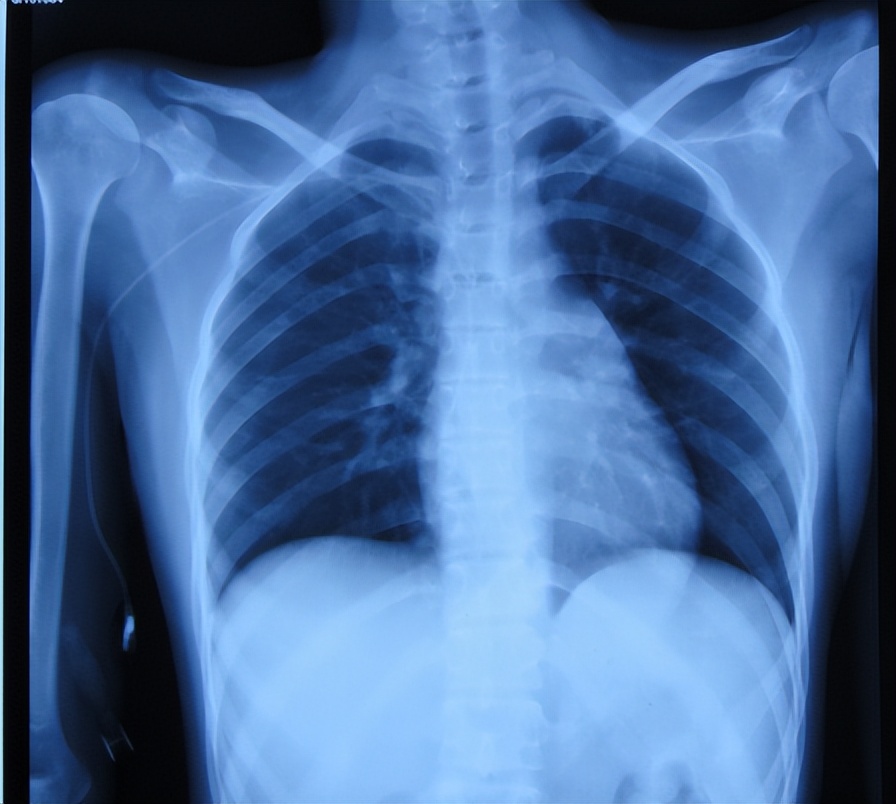

入院时查脑CT示双侧外侧裂池、欢池、鞍上池狭窄,密度增高,第三、四脑室、双侧侧脑室增宽,考虑脑膜结核、结核瘤形成导致脑积水,颅内可疑多发结节状密度增高影;考虑结核可能( 图-9 ),肺片示有感染( 图-10 )。

图-10: 2017年5月18日肺片